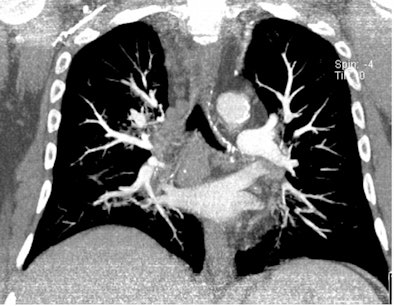

| All three CT images are from the same female patient weighing 95 kg with no pulmonary emboli. Above are two coronal maximum intensity projection (MIP) images, and below is a 1-mm thin transverse slice. At this body weight, 80-kVp CT angiography protocols provided good image quality and a high enough diagnostic confidence to exclude pulmonary embolism. All images courtesy of Dr. Zsolt Szücs-Farkas. |

A cohort comprising 100 patients with suspected pulmonary embolism (no other exclusion criteria) underwent CT angiography (Somatom Sensation 16, Siemens Healthcare) at 80 kVp, using real-time automatic mAs-modulation (CareDose 4D) and a reference mAs of 150, following an injection of 75 mL contrast medium at 3 mL/sec. The patients were divided into six groups by weight.

Szücs-Farkas concluded that "80 kVp gives sufficient diagnostic image quality at low exposure in patients weighing up to 100 kg."

There were no significant differences measured in image noise between patient groups above 50 kg and contrast-to-noise ratio in the 71-80 kg, 81-90 kg, and 91-100 kg groups. There also were no significant differences between all patient groups in the subjective ranking of enhancement, detectable ramification of the pulmonary arteries, subjective grading of noise in the vessels and mediastinum, or overall image quality.

The mean attenuation of the pulmonary arteries exceeded 300 HU in all body weight groups.